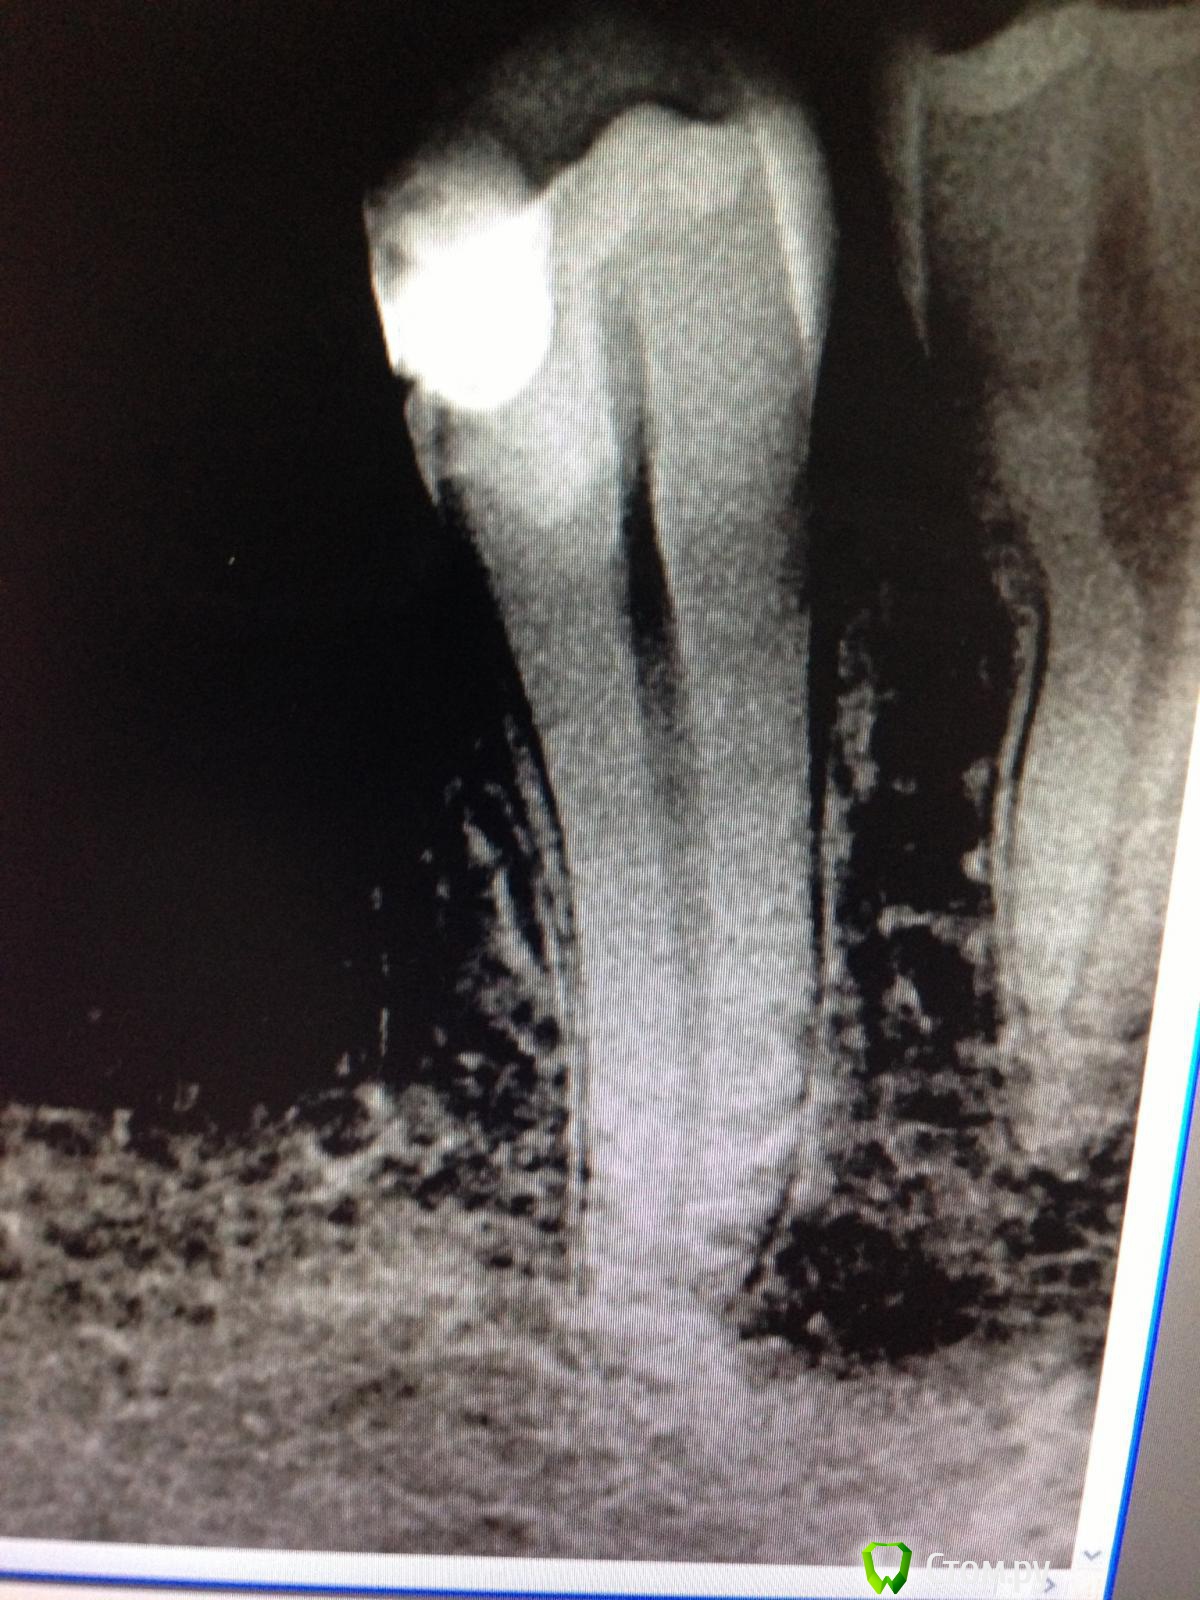

SSTi Опубликовано 26 мая, 2014 Автор Поделиться Опубликовано 26 мая, 2014 " Керамические "пульпиты( депульпировал по мк). 45. Дистально старая пломба. Доступ. Коффер. Протейперы машинные до ф2, профайлы, стоп упор 30.02. Гипохлор, аш два о, хлоргексидин. Уз. Латералка. 35. Стоп упор 40.02. Ссылка на комментарий